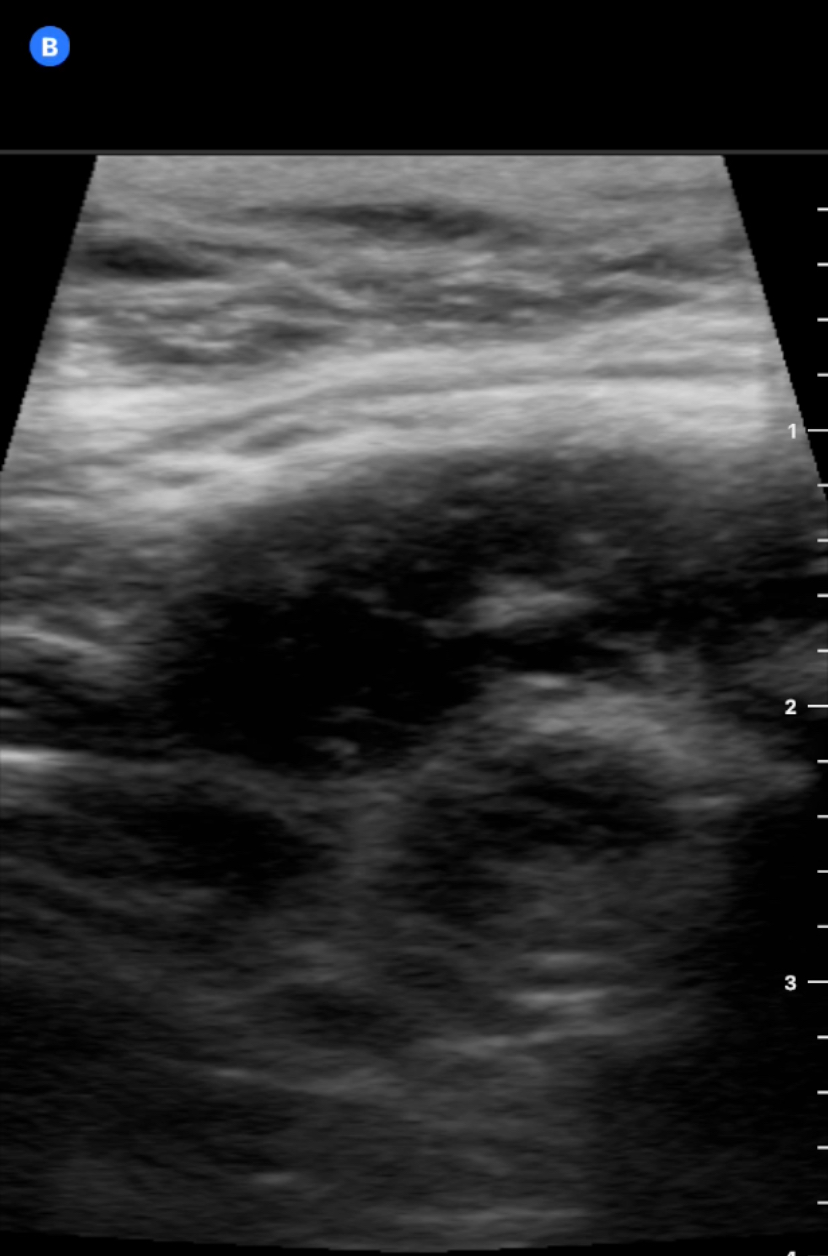

Paciente 3: con sonda lineal vemos asa intetinal engrosada (imagen de donut) y heterogenicidad alrededor del asa sugerente de abscesificación, se remite urgencias y se diagnostica de apendicitis abscesificada.